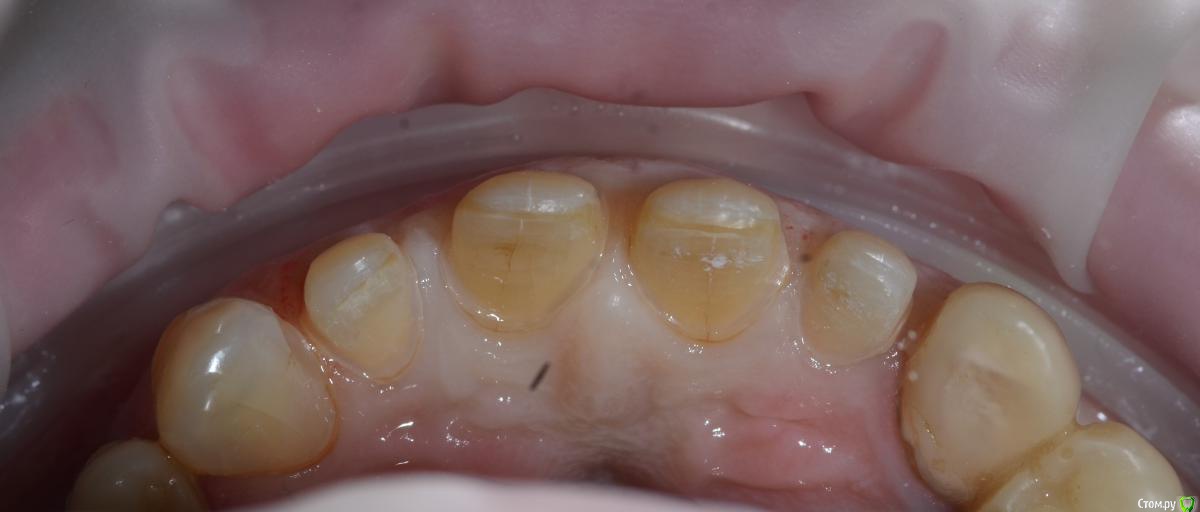

Карен Аванесов Опубликовано 5 апреля, 2016 Поделиться Опубликовано 5 апреля, 2016 есть ли фото с язычной стороны? Ссылка на комментарий

togrul Опубликовано 5 апреля, 2016 Автор Поделиться Опубликовано 5 апреля, 2016 Скажите,какие зубы были оставлены витальными?Все зубы остались витальными . 1 Ссылка на комментарий

togrul Опубликовано 5 апреля, 2016 Автор Поделиться Опубликовано 5 апреля, 2016 есть ли фото с язычной стороны? Есть фото только вч Ссылка на комментарий